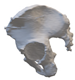

After smoothing the mask to remove surface roughness due to the low resolution of the diagnostic imaging, the hemi-pelvis with significant bone defect was printed using a Stratasys F270 (Stratasys Ltd., Rehovot, Israel) fused deposition modeling (FDM) 3D printer. A square grip was attached at the sacrum in such a way that the model could be exposed on a stand and used as a reference to facilitate the spatial orientation in the OR.

Therefore, the aiming device was first validated on a virtual 3D model. The entry and exit points and the path it takes through the bone were clearly visible in the design software, using the semi-transparent display mode. Then, the 3D-printed targeting model was fitted to the previously printed hemipelvis with its actual dimensions. The accuracy of the aiming was also verified by test drilling. The assembled model was then available to the surgeon in the OR for visual inspection, which helped to ensure spatial orientation (Figure 3).

Figure 3.

The 3D-printed hemipelvis with the aiming device in the OR.